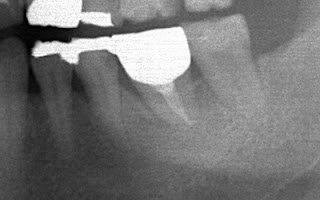

| 右下7の欠損 一番奥は歯がないままでもそこそこ咬めるので、無理にインプラントにしなくてもいいのですが 患者さんからの希望が強い場合は、インプラント治療を行っています |

| いい位置に埋入できました 手前の歯根に合わせて近心傾斜させてあります |

| 3ヶ月後に歯が入りました 計画通りアクセスホールも理想的な位置にきました 一番奥の歯は大きな力が加わる部位なので、金属製を推奨しています 手前の咬みにくそうなクラウンもいずれやり直したいですね |